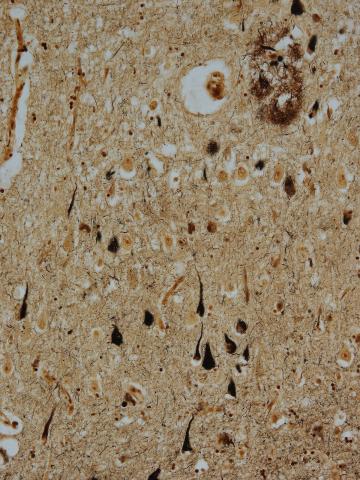

The focus of the research revolves around a protein called “tau.” Ordinarily, it helps the trillions of nerve cells in the brain communicate with one another by keeping the pathways between them straight and orderly.

But for the 5.8 million Americans currently living with Alzheimer’s (a figure that is projected to rise to nearly 15 million by the year 2050), things look different. In many cases, the normal function of tau protein collapses, allowing “tangles” to form in the brain and disintegrating the pathways between nerve cells. How and why that happens is still a mystery.

Brain tangles are also found in two other medical conditions. One is chronic traumatic encephalopathy (CTE), a disease that has received attention for its connection to contact sports like football. The other is Down syndrome, which is closely tied to Alzheimer’s: 80% of those born with an extra 21st chromosome will develop the disease as they age.